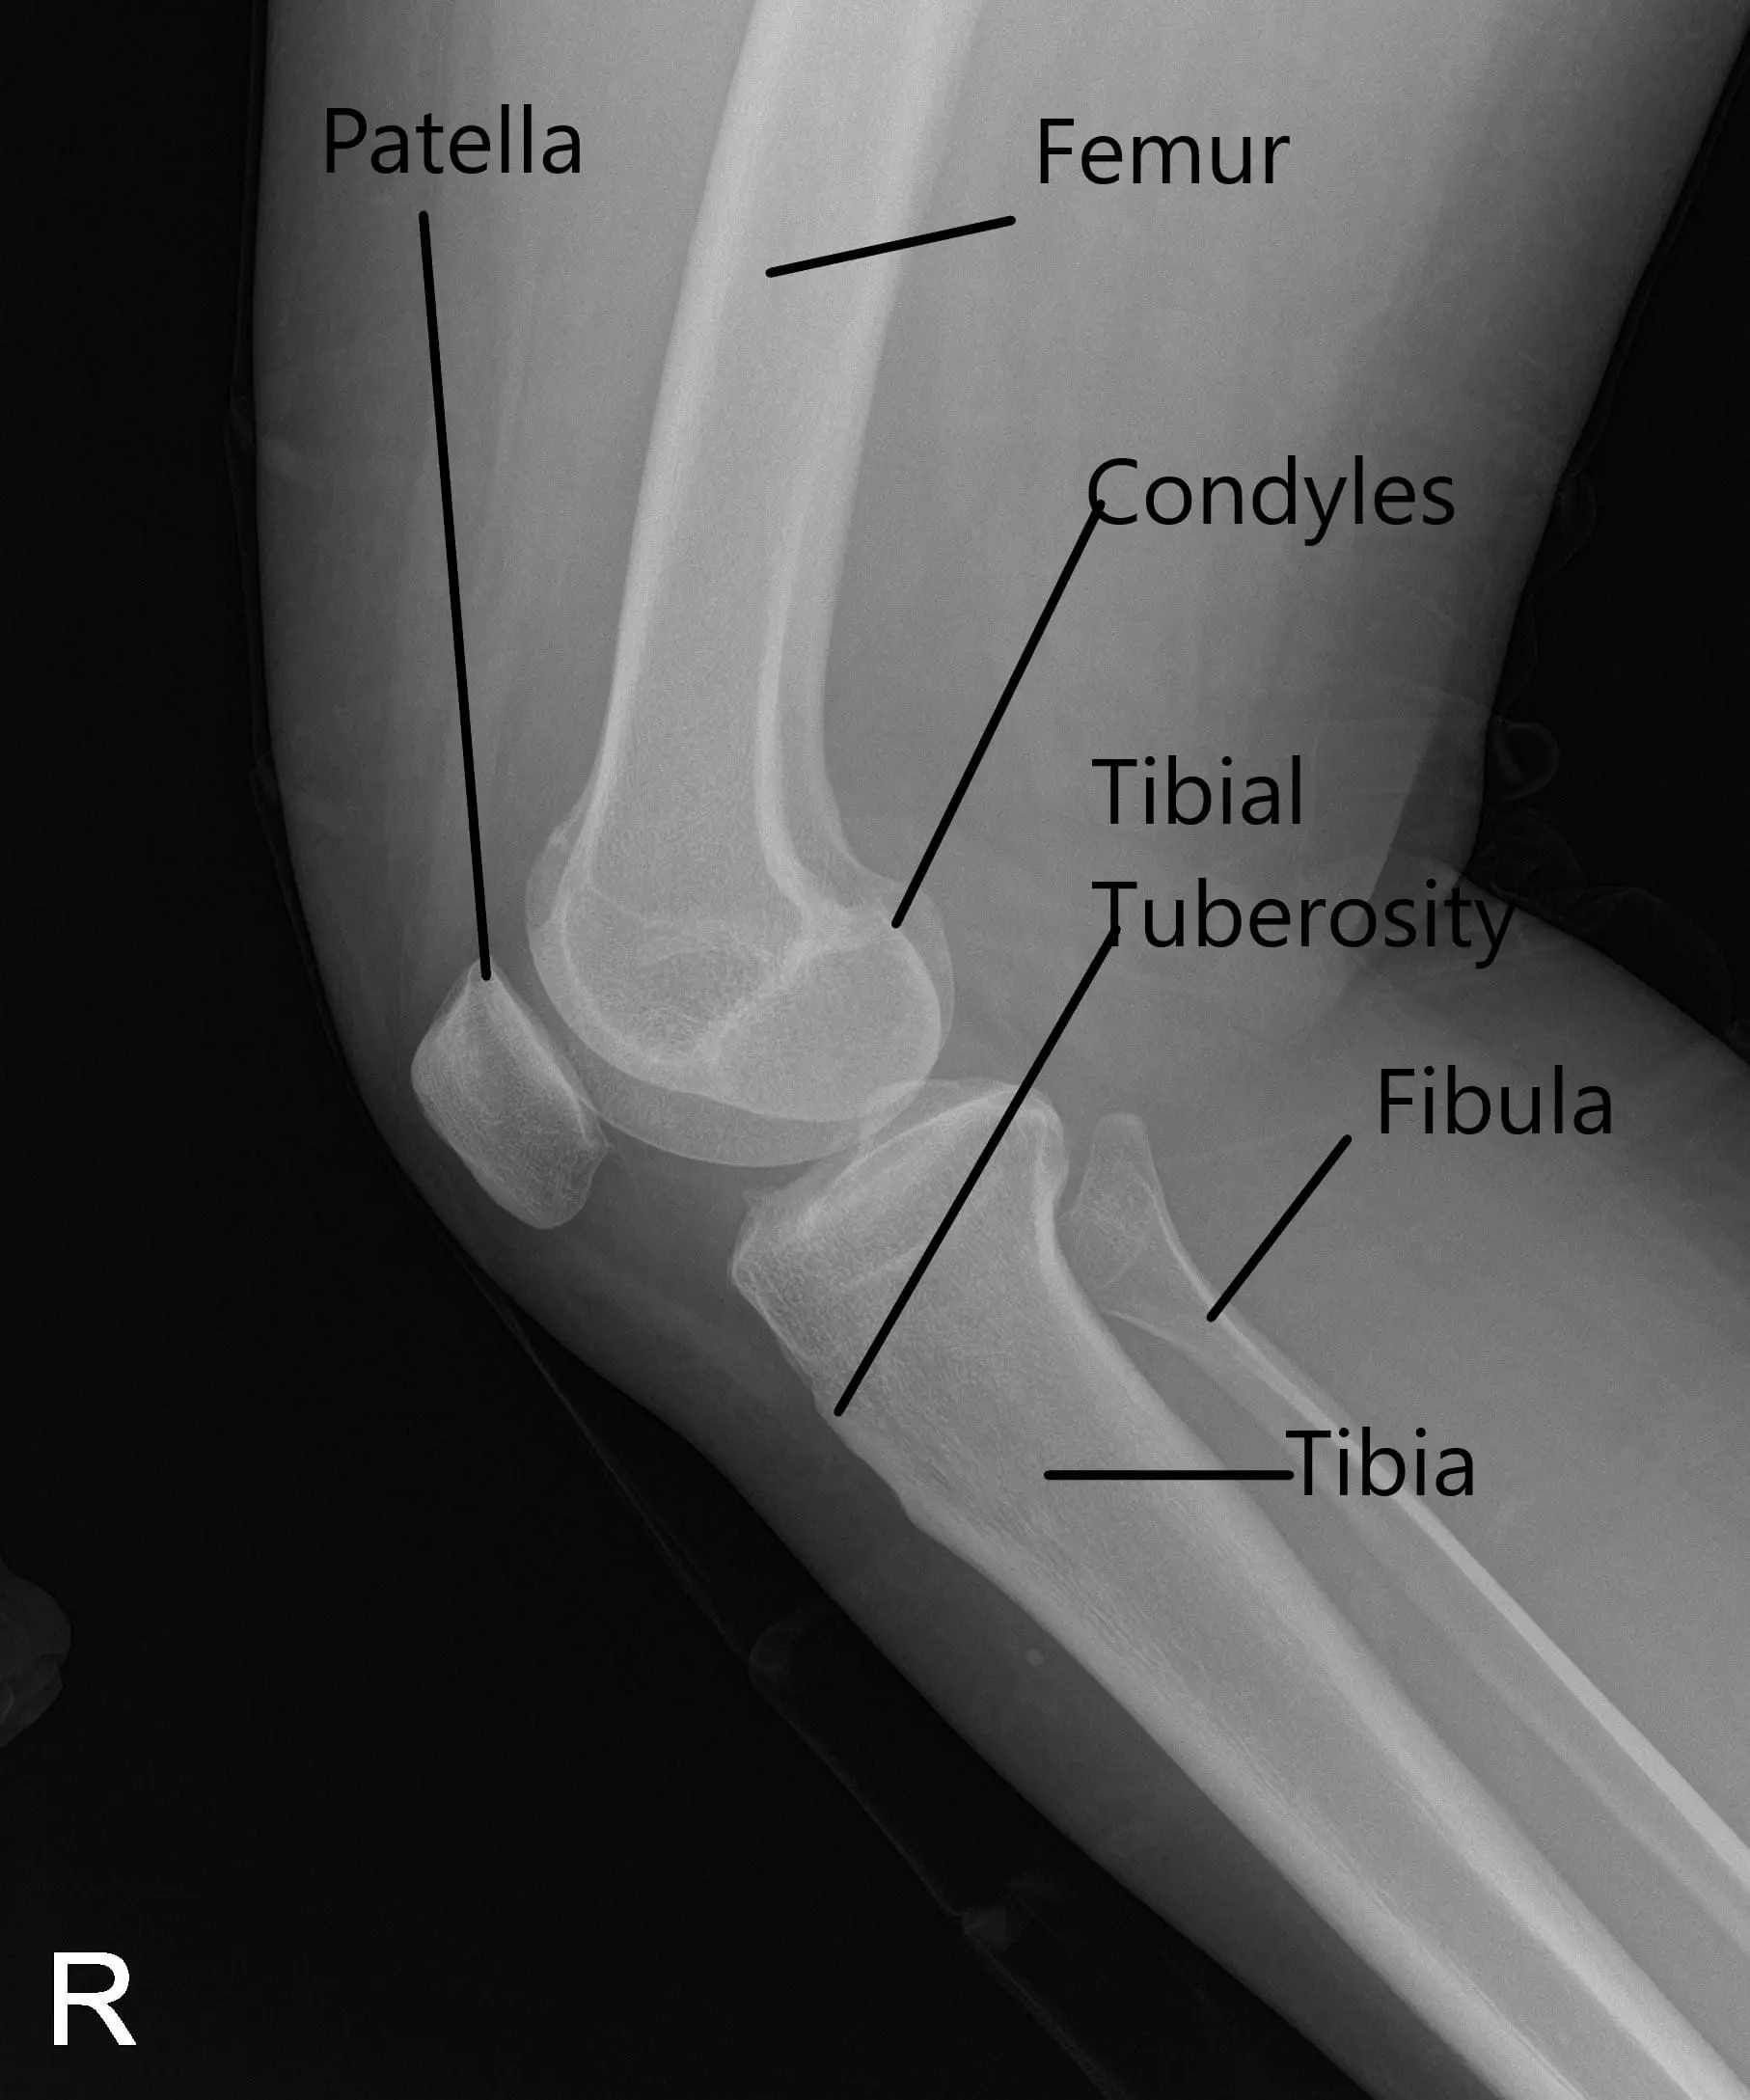

X-Ray of the right knee suggested mild osteoarthrosis in the medial and anterior compartment of the knee.